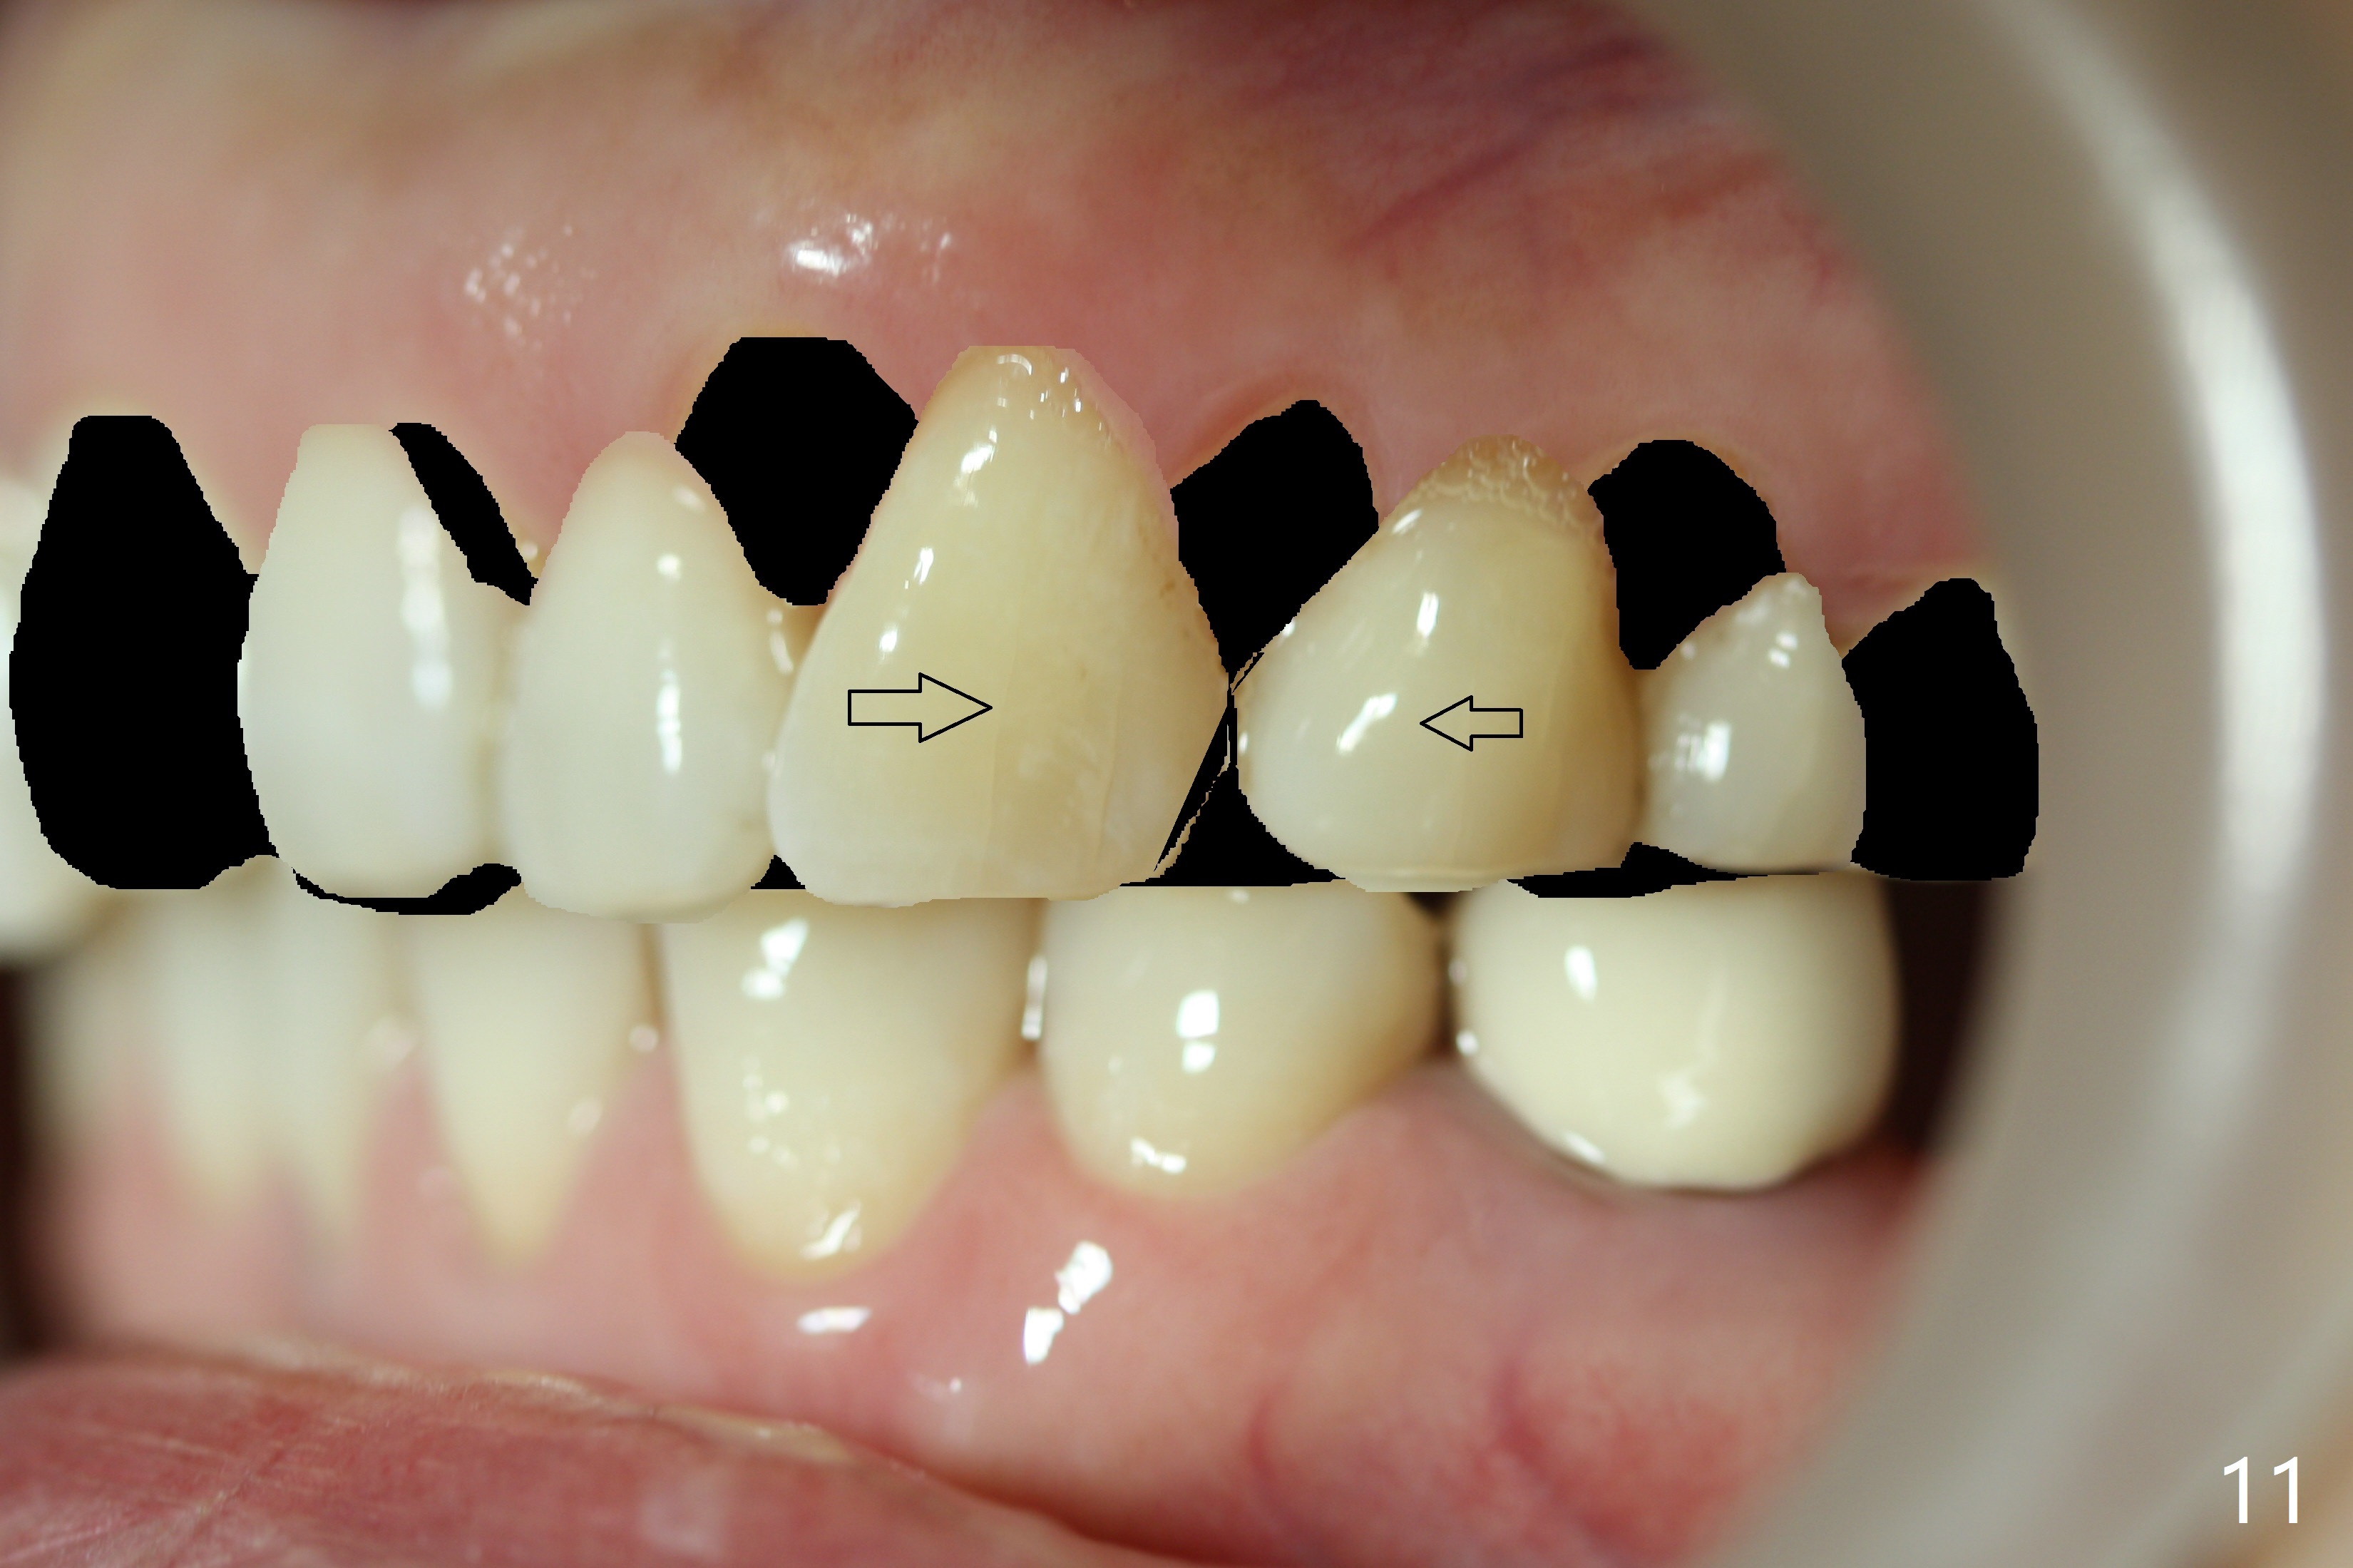

A 48-year-old woman is interested in orthodontic treatment, but is also concerned about whether there will be more loose teeth after treatment (Fig.1-8). The most critical reason for orthodontic treatment is potential recurrent caries in the lingual pit of UR2 and ultimate loss of the tooth if local crowding is resolved (Fig.10).

In addition, the upper dental midline deviates (Fig.2). It appears necessary to extract U4s (Fig.6,8: X) for realignment (Fig.9,11). When UR1 is intruded orthodontically (compare Fig.6,7 with 9) without increased mobility, it will be retained with lingual retainer. Otherwise it will be extracted for implant. Model surgery confirms the necessity of U4 extraction.